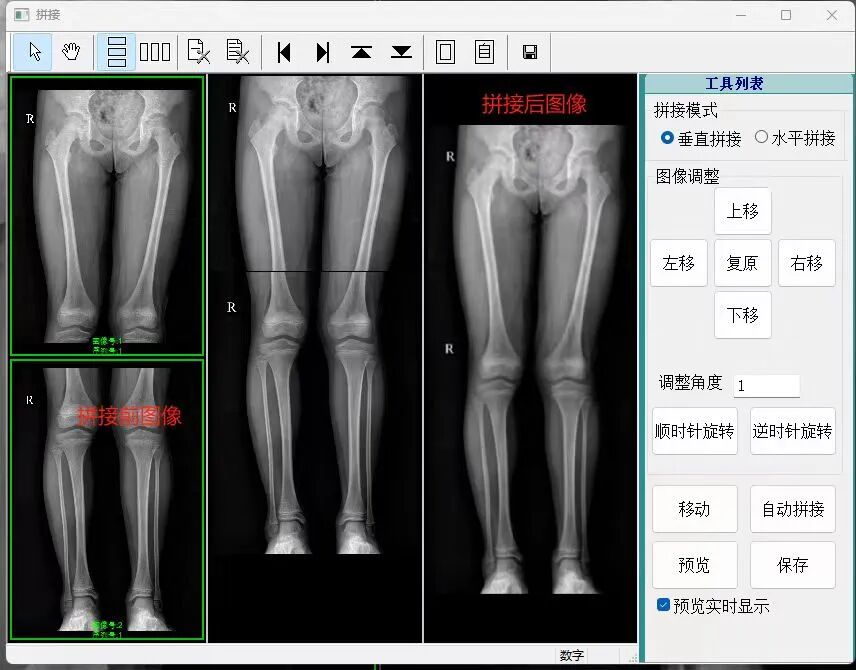

• 图像自动拼接功能(选配)

图片